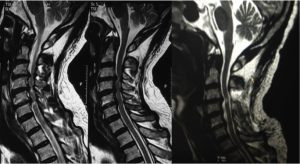

CERVICALSPONDYLOSIS AND SLIP DISC

Cervical spondylosis is a process of wear and tear of the discs between our neck bones. Due to this wear and tear, the water content in the disc decreases. As a result of this, the normal load bearing capacity of the disc is compromised resulting in neck pain. Mostly, cervical spondylosis is caused by your own tendency or genetic make-up but a small contribution may be because of smoking and minor or major injuries. Most cases of cervical spondylosis cause only neck pain. But some patients may develop nerve or spinal cord compression from a slip disc or osteophytes (bony overgrowth).

Instead of an isolated nerve, when the entire spinal cord is pressed from a slip disc, osteophyte (bony overgrowth) or ligamentous overgrowth; this condition is referred to as Cervical Myelopathy. This is a serious condition, which needs to be recognized and addressed as early as possible. Otherwise, it can result in irreversible paralysis.

As this is an irreversible and progressive condition, the treatment for this condition is always surgical. Depending on whether the compression is from front of the neck or behind the neck, decompression can either be done from the front (ACDF or ACDR) or from behind (Cervical Laminectomy with or without fusion or Cervical Laminoplasty).